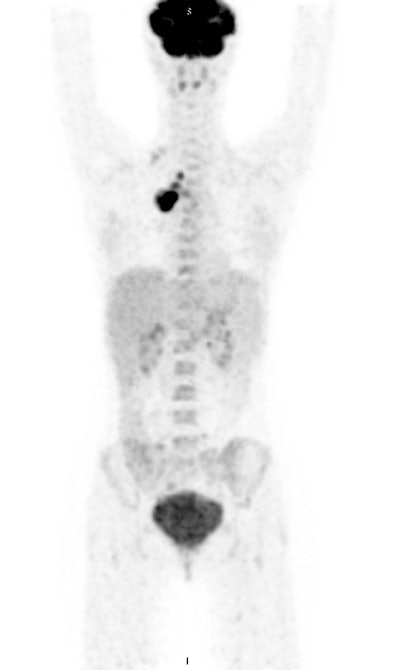

Certain quantitative PET parameters can help clinicians predict how well patients with Hodgkin's lymphoma will react to their treatment, according to preliminary results from a study conducted in the Ukraine and presented at ECR 2018 in Vienna.

In a comparison of several variables, the researchers found that metabolic tumor volume and mean standard uptake values (SUVmean) were statistically significant indicators of event-free survival.

The use FDG-PET/CT is a well-established method for evaluating patients with Hodgkin's lymphoma and is considered the gold standard for imaging the progression of the disease. The hybrid modality also is the primary choice for staging, restaging, and response to therapy.

The aim of this study was to retrospectively calculate and analyze metabolic quantitative PET parameters in patients with Hodgkin's lymphoma, and to evaluate possible correlations between quantitative PET indicators and event-free survival among these patients.